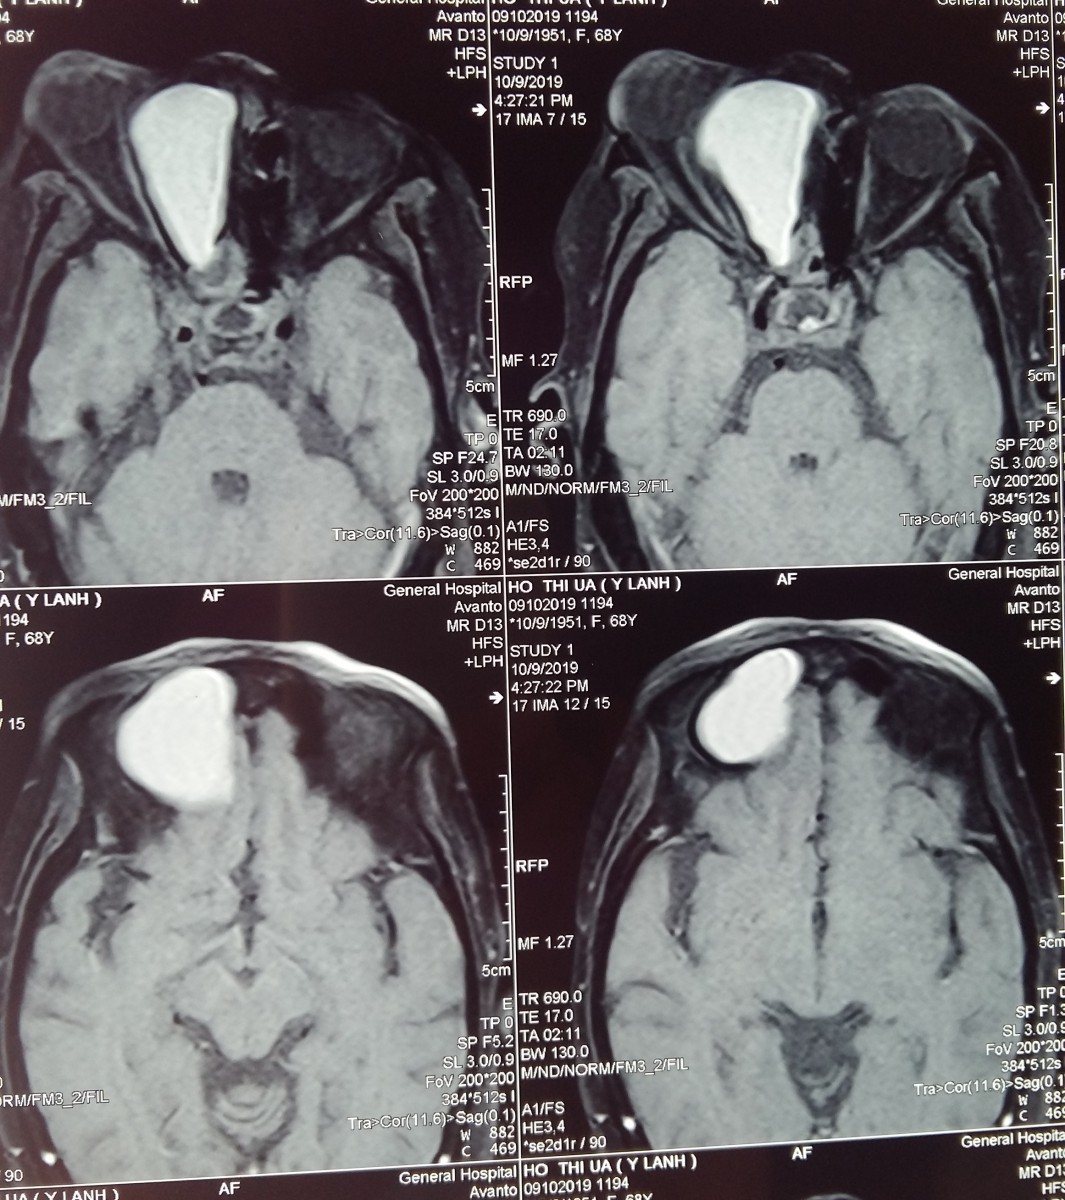

Kết quả đo thị lực, chụp MRI và CT-Scan tại Bệnh viện ghi nhận một khối u nhầy xoang sàng phải với kích thước 53 mm x 36 mm x 49 mm đã xâm lấn vào trong hốc mắt, chèn dây thần kinh thị giác phải, chèn ép cơ thẳng trong đẩy nhãn cầu lồi ra ngoài và ăn mòn sàn sọ trước.

Hinh anh khoi u nhay trong hoc mat

Hình ảnh khối u nhầy xoang sàng trong hốc mắt, chèn dây thần kinh thị giác phải